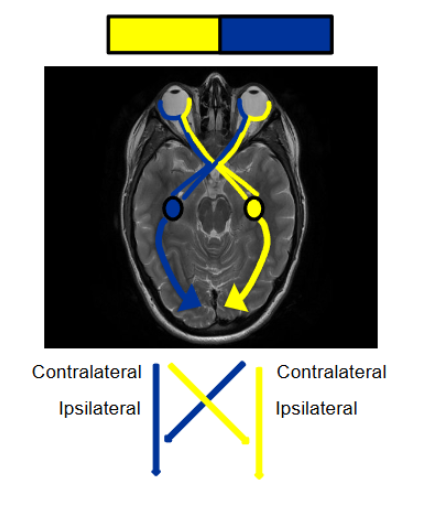

ipsilateral is same side contralateral is opposite